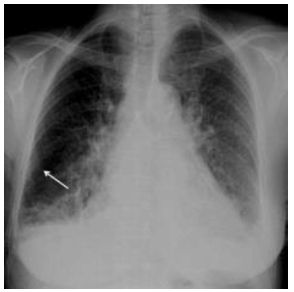

Analise a imagem abaixo para responder à questão.

Considerando a radiografia acima, analise as proposições abaixo.

I. Observa-se que é um paciente do sexo masculino.

II. Radiografia de tórax em PA, demonstra infiltração intersticial reticular bilateral e difusa associada à cardiomegalia.

III. Na porção lateral do pulmão direito identificam-se opacidades lineares perpendiculares à pleura (seta), características de linhas septolinfáticas ou linhas B de Kerley.

É correto o que se afirma em